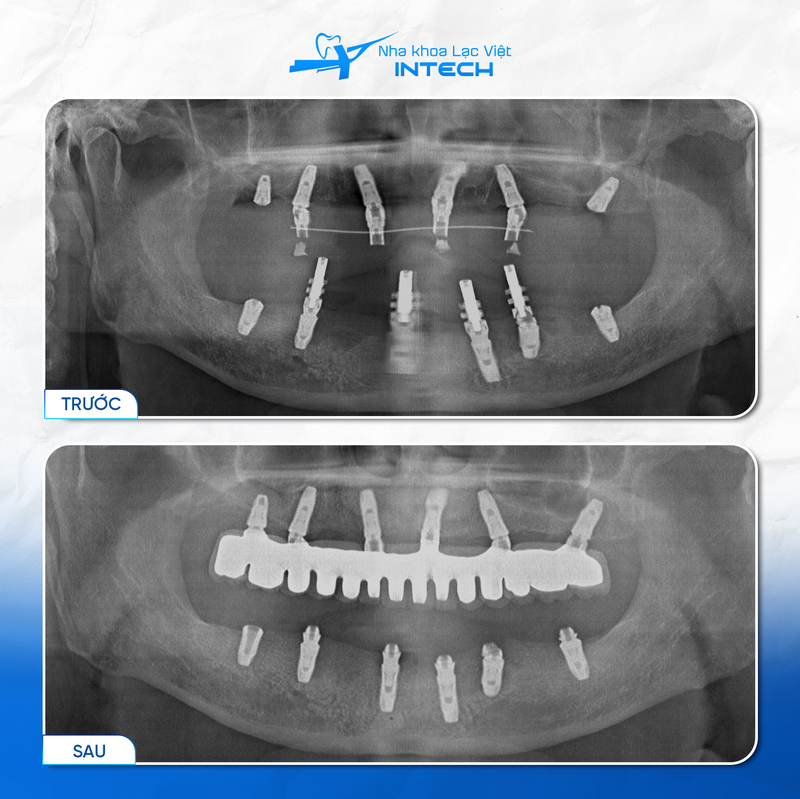

Bác sĩ sẽ sử dụng máy chụp phim CT Cone Beam để thu thập chính xác các dữ liệu, từ đó phân tích cấu trúc xương hàm, xác định mật độ xương, thể tích xương cũng như vị trí các dây thần kinh. Kết quả này giúp bác sĩ đưa ra phác đồ điều trị chính xác, đảm bảo quá trình cấy ghép Implant diễn ra an toàn và hiệu quả.

Bác sĩ sẽ tiến hành cấy ghép trụ Implant vào xương hàm, tránh các tổ chức quan trọng theo phim chụp CT Cone Beam